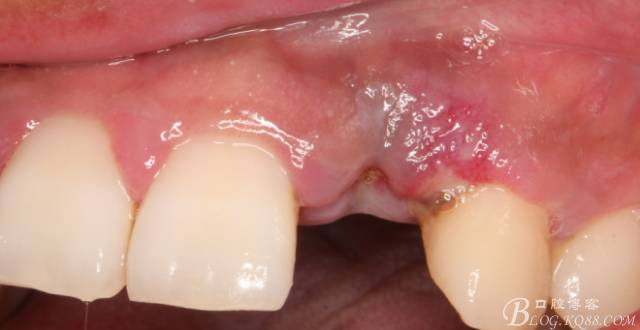

10天拆線一切正常,又過了兩周患者復(fù)診,自述期間無異常??趦?nèi)檢查,真的嚇了一跳,唇側(cè)鼓了個包,擠壓有白色分泌物溢出,絕對不是膿液,液體排除后,術(shù)區(qū)觸診空虛,外觀塌陷。這時候考研大夫的時刻到了,是先觀察一段時間再說?還是馬上進行處理?我的回答是:馬上處理!如果你沒有及時處理,而是放患者回家觀察,那么接下來會發(fā)生如下情況:1.回家后患者家屬及親友會有很多你可以想象得到的討論;2.患者及家屬會對你產(chǎn)生不信任,勢必會到其他門診或醫(yī)院檢查,他院大夫會不會發(fā)表對你不利的言論;3甚至?xí)蚁嚓P(guān)法律界人士找你討要說法。